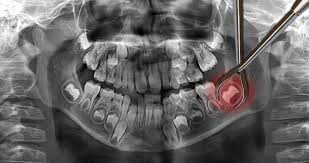

Wisdom Teeth

If you’re a teenager or young adult and your wisdom teeth are growing in, make a dentist appointment to assess whether or not they’ll need to be pulled.

If you let them grow in without this advice, there might not be room in your mouth for all your new teeth. That can lead to an impacted wisdom tooth, which can lead to a really painful infection called pericoronitis.

If your wisdom teeth have already grown in, check them out in the mirror to see if your gums are beginning to grow over them. Sometimes, a gum flap will develop. This is the leading sign of pericoronitis.

If you see these signs and symptoms around your wisdom teeth, make a dentist appointment soon to avoid infection!